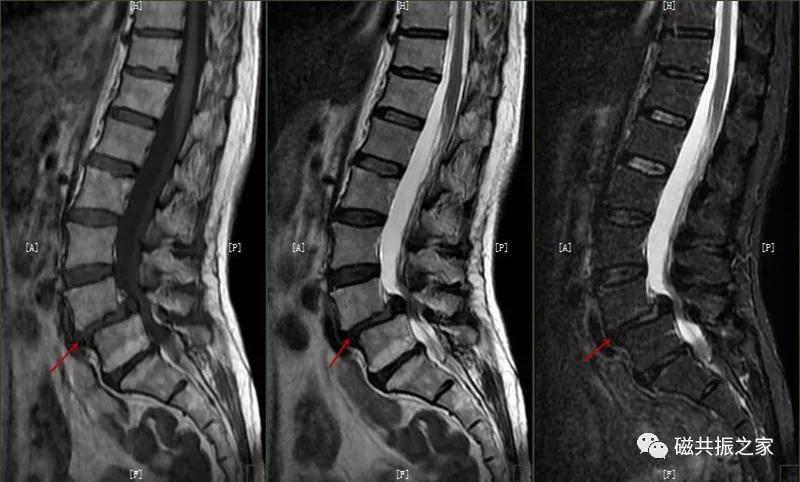

在矢状面上T1WI和T2WI显示各椎体楔形变,椎体高度减小,椎间隙变窄。椎体后1/3区呈多发性小骨质凹陷的Schmorl结节改变,髓核组织突入其中,边缘清楚,常呈上下对称分布,青少年病变周围可见长T1长T2信号,提示骨小梁水肿。

许莫尔结节(Schmorl,snodes),是休门病的一个病例征象。1930年Schmorl对照检查8000例尸检和X线发现椎体生长板发育不完善,或后天外伤致椎间盘突入椎体骨松质内,形成椎体压迹,是休门病的主要征象之一。除休门病外,其他的原因引起的生长板破坏,也可能产生Schmorl结节样改变。

矢状面显示椎体上或下椎间盘面异常信号,常呈长T,长T2信号,见髓核信号突入椎体内,常伴椎间隙变窄,常见于L3~S1椎体。